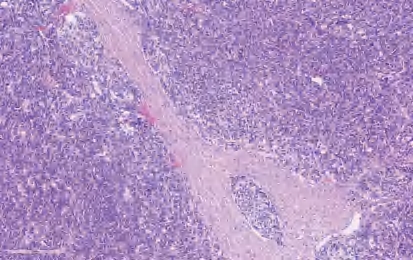

【定义】类癌是恶性LNEN伴分化良好的器官样结构,它包括两类:典型类癌(TC),核分裂<2个/2 mm 2 ,缺乏坏死(图2-13);不典型类癌(AC),核分裂为2~10个/2 mm 2 和(或)坏死,通常为点灶状(图2-14)。

图2-13 TC

【镜下形态】TC和AC为分化好的NET伴有独特的肿瘤结构和细胞学特征。肿瘤细胞为小至中等大小,呈立方形、多角形或梭形(梭形细胞尤其易发生在周围型病变中),形态较一致,核仁不明显,核染色质呈细颗粒状、中至大量嗜酸性颗粒胞质。临床上TC为低级别,AC为中级别,二者的区别在于核分裂象和有无坏死。也可见到嗜酸性颗粒细胞、透明细胞和含色素的类癌。与LCNEC和SCLC不同,伴有SCC或腺癌的复合型类癌不常见。此外,类癌不与SCLC和LCNEC混合存在。罕见的类癌,形态符合不典型类癌,但核分裂象>10个/2 mm 2 或Ki-67增殖指数偏高(>30%),有限的病例基因学分析显示其与类癌关系密切,而不是SCLC和LCNEC(缺乏RB1或TP53基因突变,低的总肿瘤负荷或MEN1基因突变的存在)。类癌肿瘤细胞呈低分子CK阳性,高分子CK阴性;神经内分泌标记CgA、Syn、CD56、INSM1呈强阳性。周围型肿瘤TTF-1呈阳性,中央型肿瘤TTF-1呈阴性。尽管Ki-67增殖指数>5%更可能是AC,但Ki-67的增殖指数不是肺类癌的诊断标准,尤其在TC与AC的鉴别中。Ki-67的主要作用是在挤压的细胞学或小活检中排除SCLC或LCNEC。